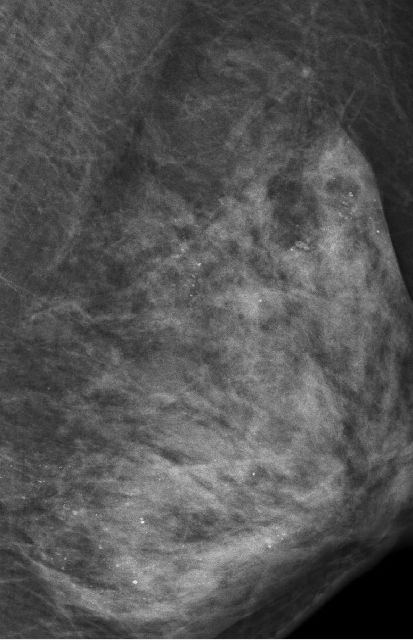

最让医生意外的是她的左侧乳房。乳腺X线检查时,发现里面全部都是细小如沙子一样的钙化灶,布满整个乳腺。

在X光片下,朱女士的乳腺里满是星星点点的钙化灶

让管床医生陶龙犯难的是,如此多的细小钙化灶,无法判断哪些是良性哪些是恶性。

乳腺沙砾样钙化灶是乳癌的信号之一,需要高度关注。

为进一步确诊,朱女士接受了左侧乳腺核磁共振检查,没有发现大的异常,暂时排除了恶性的可能。“但仍处于高危状态。”